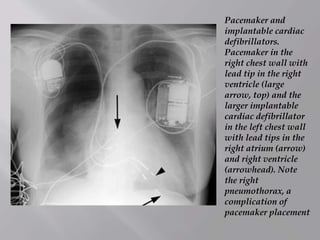

Pacemaker and

implantable cardiac

defibrillators.

Pacemaker in the

right chest wall with

lead tip in the right

ventricle (large

arrow, top) and the

larger implantable

cardiac defibrillator

in the left chest wall

with lead tips in the

right atrium (arrow)

and right ventricle

(arrowhead). Note

the right

pneumothorax, a

complication of

pacemaker placement

Epicardial implantable cardiac defibrillator patches (arrows) that required